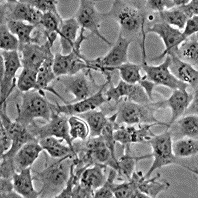

Морфология: эпителиоподобная

Способ культивирования: монослойный